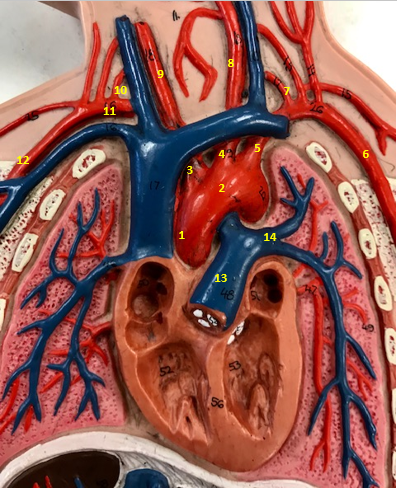

Aorta

Name #2

Brings blood out of left ventricle

Function of aorta

Brachiocephalic artery

Name #3

Supplies oxygenated blood to right arm shoulder neck and head

Function of brachiocephalic artery

Left common carotid artery

Name #4

Supplies oxygenated blood to left neck and head

Function of left common carotid artery

Left subclavian artery

Name #5

Supplies oxygenated blood to left arm shoulder

Function of left subclavian artery

Left axillery artery

Name #6

supplies blood to left armpit and upper limb

Function left axillary artery (6)

Left vertebral artery

Name #7

Supplies blood to brain and spinal cord

Function of left vertebral artery (7)

Left common carotid artery

Name #8

Supplies blood to left neck and head

Function of left common carotid artery (8)

Right common carotid artery

Name #9

Supplies oxygenated blood to right neck and head

Function of right common carotid artery (9)

Right vertebral artery

Name #10

Supplies blood to brain and spinal cord

Function of right vertebral artery (10)

Right subclavian artery

Name #11

Supplies blood to right arm and shoulder

Function of right subclavian artery

Right axillery artery

Name #12

Supplies blood to right armpit and upper limb

Function of right axillery artery (12)

Pulmonary trunk

Name #13

Bring blood out of right ventricle to lungs

Function of pulmonary trunk (13)

Left pulmonary artery

Name #14

Bring blood to left lung

Function of left pulmonary artery (14)